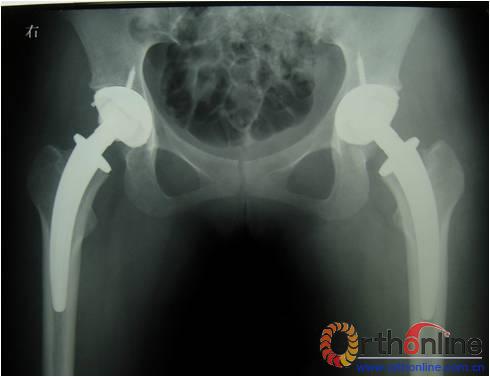

图为:方某,女,21岁,双侧激素性股骨头坏死,ARCO III-C期,C.F.P. 股骨假体THA前后双髋X线摄片。

图1、图2:术前;图3:术后;图4:术后3个月;图5:术后6个月;图6:术后1.2年